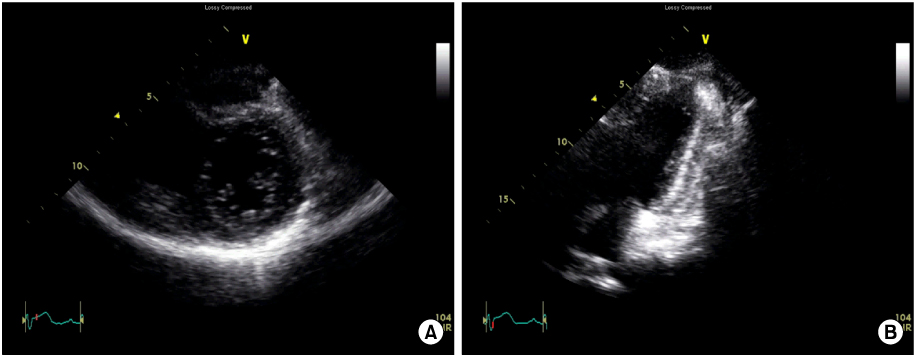

Fig. 3A). At day 3, dyspnea was aggravated and rales were audible in both lung fields. Follow-up 2D echocardiography showed prominent myocardial edema and severe diffuse hypokinesis in both ventricles with mild circumferential pericardial effusion. LVEF was 20%, while the septal and the posterior wall thickness were 13.2 mm and 12.5 mm, respectively (

Fig. 4Two-dimensional echocardiography at day 2 showing diffuse hypokinesis of left ventricle with severe systolic dysfunction. Mild pericardial effusion is noted. (A) Parasternal short axis image. (B) Apical two chamber image (Video clip of this figure is available at

http://emj.ewhamed.ac.kr/journal/view.html?Vol=035&Num=02&page=129).